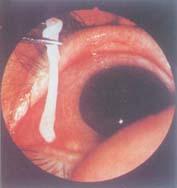

曼氏迭宫绦虫又称孟氏裂头绦虫,成虫主要寄生在猫科动物,偶然寄生人体。但其裂头蚴可在人体寄生,导致曼氏裂头蚴病,其危害远较成虫为大。(注:例图为经手术从一例用蛙敷眼后的患者眼部取出的裂头蚴。)